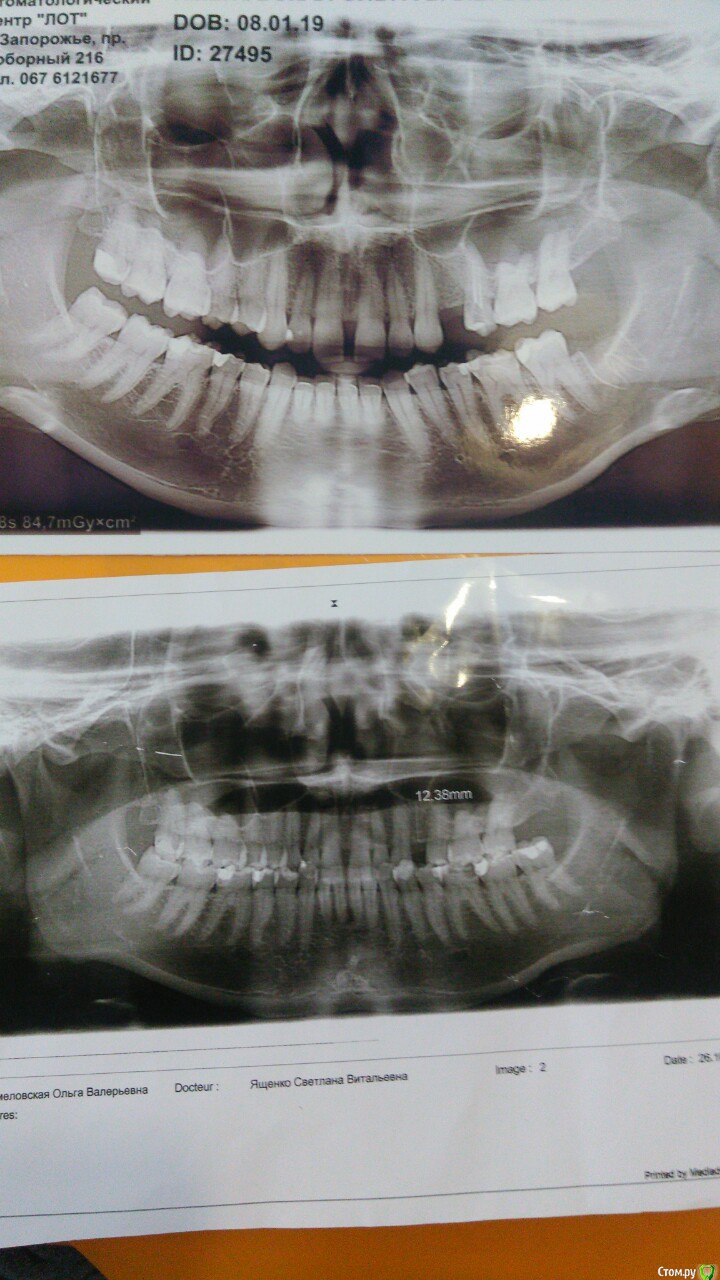

Здравствуйте. Сделала новые  снимки. Стоматологи пролечили пятерку сверху. Вроде полегчало. Невропатолог приписал тоже лекарства сказал нерв. Но что то они не помогают. Как болело так и болит по ощущениям между 6 и 7, выделения есть соленоватого вкуса. По ощущениям между 6 и 7. нос не заложен. Гайморита нет. При наклоне головы вниз. Дискомфорт как будто чувствую корень шестерки, тянет. И начинает ныть. Временами пульсирует (неприятно) тоже между 6 и 7. внутри. Что это может быть. спасибо.

post-56737-0-09905600-1547909663_thumb.jpg